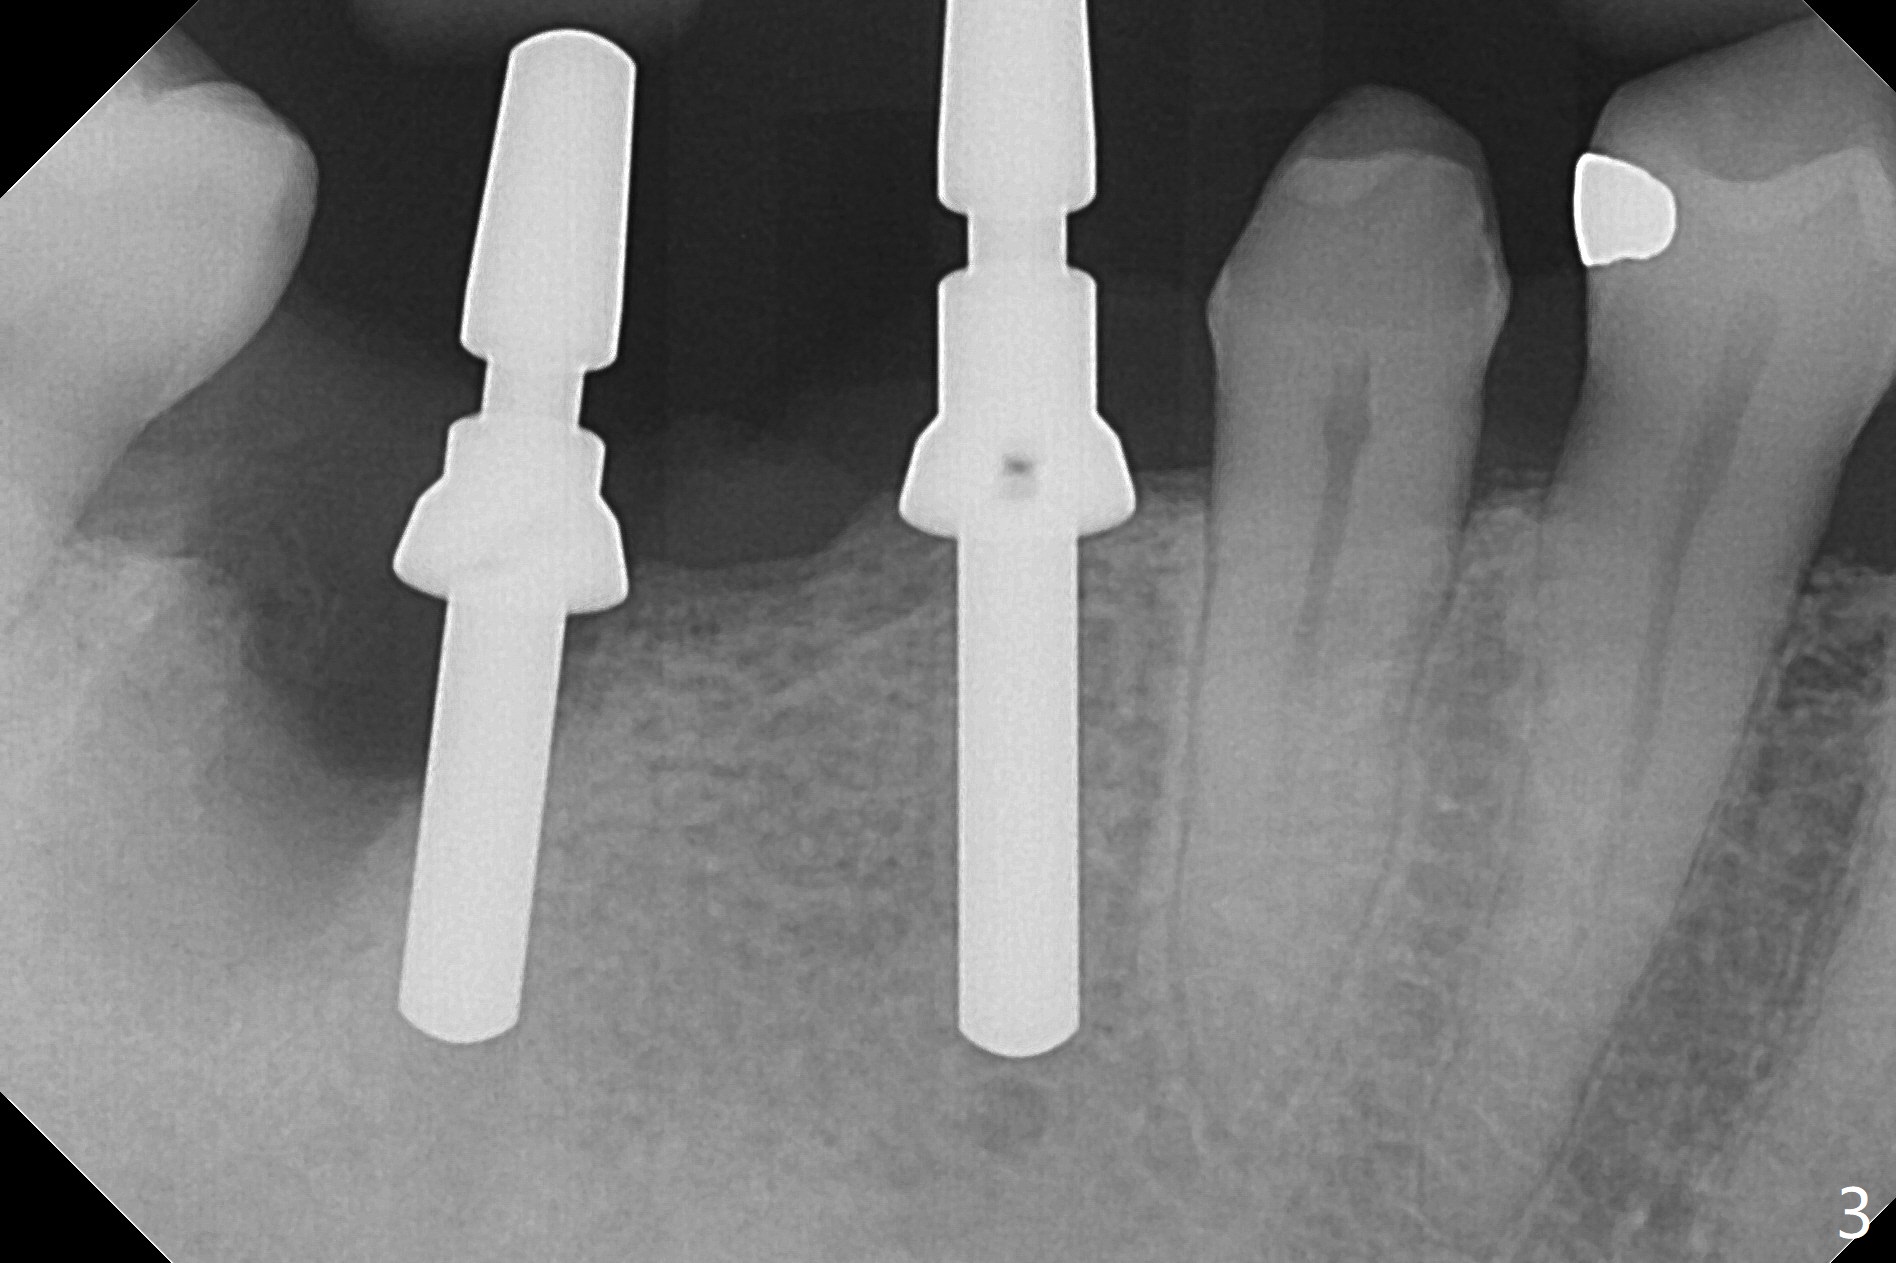

The edentulous area at #30 looks narrow after #31 extraction (Fig.1) and after incision (Fig.2). As planned, osteotomy is established at #30 as a premolar and at the mesial slope of #31 socket (Fig.3). Following adjustment of the trajectory at #30 and sequential osteotomy until 3.5x11.5 mm, two of 4x10 mm dummy implants are inserted with stability as well as dummy abutments (Fig.4). Final implants are 4x11.5 mm with insertion torque > 50 Ncm; after suturing, abutment margins are subgingival, particularly at #31 (Fig.5 (*: Vera Graft)). Periodontal dressing is applied. Provisional will be fabricated when the wound heals. It appears that the small and regular implants are appropriate for the narrow mesiodistal space at #30 and 31. There appears to be bone growth around the implants nearly 4 months postop (Fig.6).